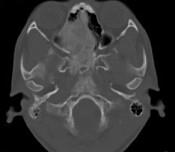

问题 女,17岁,鼻阻塞、头痛两年.如图所示符合筛骨病变最可能的诊断是()

选项 A.成骨肉瘤骨 B.纤维异常增殖症 C.软骨瘤 D.骨瘤 E.骨化性纤维瘤

答案 E